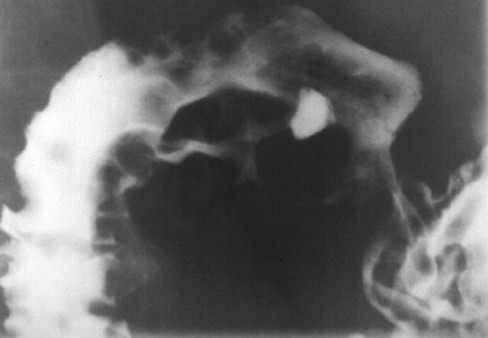

Les ulcere post bulbaire duodenale est le plus souvent

situe a D1 , D2 au niveau sus-valterien et a bord interne .Endoscopie

a cette portion est difficile . Image TOGD baryte

montre une stenose asymetrique avec image de ulcere au

millieure , aspect de "perle enfilee" .

Ulcere a bord interieure de

D2 au niveau sus-valerien . Image stenosant de

D2 avec niche remplisage de baryte . |

|

Ulcere stenosant de D2

aspect de " perle filee " avec image d'

epaississement des plies muqueuses duodenum en amont

et au aval ( duodenite ) . |